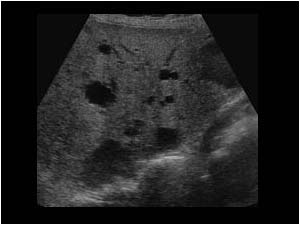

Chart this for ordering physician

Polycystic liver disease

Multiple cysts with posterior acoustic enhancement, consistent with polycystic liver disease.

What is this pathology?